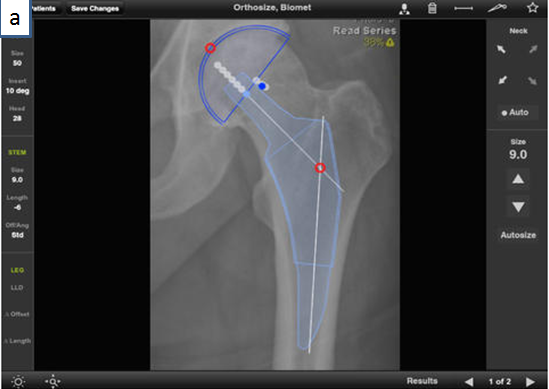

Zimmer公司在APP Store上发布的Biomet Orthosize Templating是一款多平台在线手术规划软件。该软件可用于多种人工关节置换的术前手术方案设计,辅助医生确定截骨位置、精确计算截骨量、确定假体型号及安装位置,提高手术方案的精准度。同时临床技术人员可根据术前规划确定的手术方案设计个性化截骨导板,利用3D打印技术进行截骨导板的快速制造,并应用于临床,辅助医生完成关节置换手术,此软件于2012年获得FDA认证。

(a)髋关节置换手术方案设计

图3 Biomet Orthosize Templating软件制定术前手术规划方案